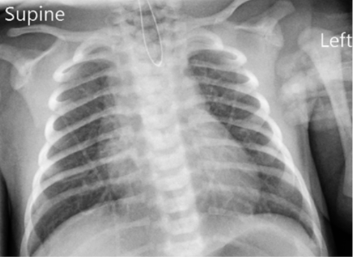

Giant Bullae as a Great Mimicker of Pneumothorax in a Symptomatic Young Adult Individual Seen on CXR and CT Chest

Fredy Rutachunzibwa, Julieth Kajugusi and Titus Kabalimu. 13(2): 01-04.